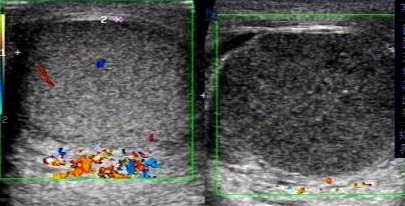

泌尿外科收治一名18歲男性青少年,反復(fù)右側(cè)睪丸疼痛2天,2天前出現(xiàn)右側(cè)睪丸疼痛稍腫脹,無(wú)其他不適,查陰囊彩超:右側(cè)睪丸、附睪較左側(cè)明顯增大,右側(cè)附睪頭實(shí)質(zhì)回聲增強(qiáng)不均,雙側(cè)睪丸、附睪血流信號(hào)未見(jiàn)明顯異常,當(dāng)時(shí)予對(duì)癥處理后疼痛好轉(zhuǎn)后回家。

近日,患者疼痛腫脹加重,再次至我院急診,行急診陰囊彩超:右側(cè)睪丸腫大回聲異常并其上方異?;芈晠^(qū),未見(jiàn)明顯血流信號(hào),未排睪丸扭曲可能,左側(cè)睪丸、附睪位置偏高,血流分布尚正常。

(左側(cè)為正常睪丸,右側(cè)為扭轉(zhuǎn)睪丸)

彩色多普勒超聲血流圖是最具有診斷價(jià)值的影像學(xué)檢查,可以詳細(xì)、實(shí)時(shí)地觀察睪丸內(nèi)的血流情況及其變化,目前被廣泛應(yīng)用于睪丸扭轉(zhuǎn)的診斷和鑒別診斷。睪丸內(nèi)動(dòng)脈血流信號(hào)明顯減少或消失是診斷本病的最可靠標(biāo)準(zhǔn)。